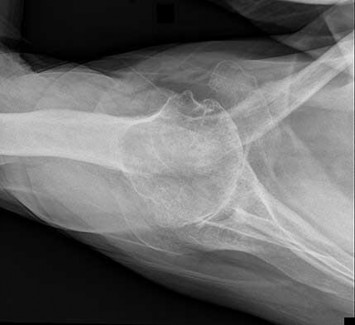

Question 4:

A 12-year-old obese male presents with left thigh pain and an antalgic gait for 4 weeks. He has been entirely unable to bear weight on the left leg for the past 2 days. Radiographs show a slipped capital femoral epiphysis (SCFE) with a slip angle of 60 degrees. What is the most significant risk factor for the development of avascular necrosis (AVN) in this patient?

Options:

- Severity of the slip angle

- Patient's weight

- Duration of symptoms prior to presentation

- Inability to bear weight

- Use of a single screw for fixation

Correct Answer: Inability to bear weight

Explanation:

The clinical inability to bear weight, even with crutches, defines an unstable SCFE according to the Loder classification. Unstable SCFE carries a significantly higher risk of avascular necrosis (AVN), historically up to 50%, compared to stable SCFE where AVN is rare. While a severe slip angle increases the technical difficulty of fixation, stability is the primary predictor of AVN.